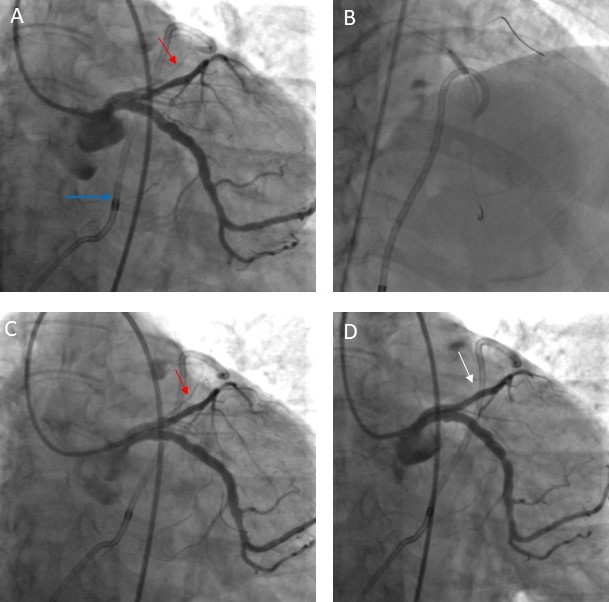

Forty-five minutes later, in the coronary care unit, the patient became tachycardic and hypotensive, and a repeat bedside echocardiogram revealed a large circumferential pericardial effusion. Urgent pericardiocentesis and removal of 200-cc hemorrhagic fluid improved the patient’s hemodynamics. She was transferred back to the catheterization laboratory. Right femoral artery access was used and an extra-backup (EBU) 4 was engaged to the left coronary system. LAD flow was intact, however, the leak was still visible (Figure 2A; Video 4). After wiring both the LAD and the left circumflex artery, prolonged inflations of a non-compliant balloon in the proximal LAD (Figure 2B) and implantation of a second zotarolimus-eluting stent (2.75 x 30 mm) in the LAD ostium, nicely overlapping the previous stent, failed to stop the leak (Figure 2C). A 3 x 20-mm PK Papyrus covered stent (BIOTRONIK AG) was then implanted in the proximal LAD to seal the perforated branch, and subsequently the active leak disappeared (Figure 2D; Video 5). The patient had an uneventful recovery and was discharged 6 days later.